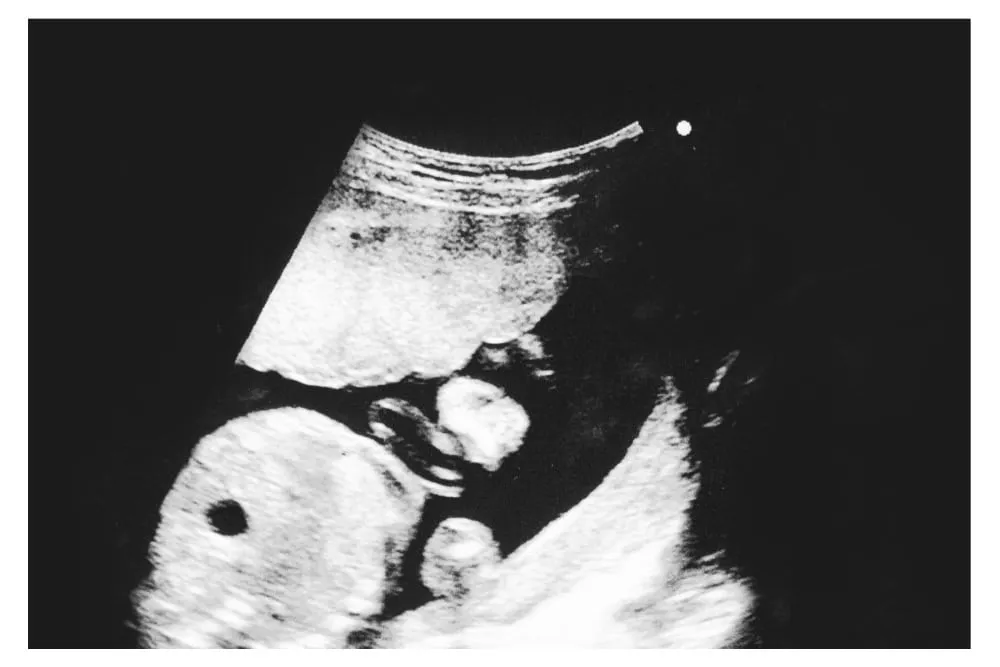

2. Hình ảnh siêu âm thai 21 tuần trong bụng mẹ

Các chỉ số sinh trắc của thai 21 tuần khỏe mạnh gồm:

- Đường kính lưỡng đỉnh (BPD): 44-55mm

- Chu vi vòng đầu (HC): 169-201mm

- Chu vi vòng bụng (AC): 143-180mm

- Chiều dài xương đùi (FL): 31-39mm.

1. Chỉ số siêu âm 4d thai 21 tuần

Thai 21 tuần phát triển khỏe mạnh thường có những chỉ số siêu âm sau đây: